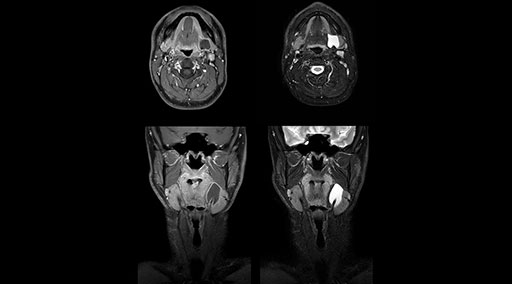

“Our DMG Lisle location includes a cancer center, so soft tissue neck scans, brachial plexus scans, and prostate scans are common. For these exams, mDIXON TSE provides excellent images with and without fat suppression all while helping us reduce repeats and work more efficiently,” Mr. Duffy says.

“With the 2-echo Philips mDIXON TSE the timing is short and the fatsat is very robust. The biggest thing is that you know your fat suppression will be good, even in thin patients or large patients that are off-center,” Mr. Sybesma says.

“mDIXON TSE raises our diagnostic confidence with its homogeneous

fat suppression. Neck exams and rheumatology patients are two examples where mDIXON TSE is especially useful,” Dr. Kaakaji says. “For us it’s also an efficiency boost in exams where we need pre and post T1-weighted images with great fat suppression.”